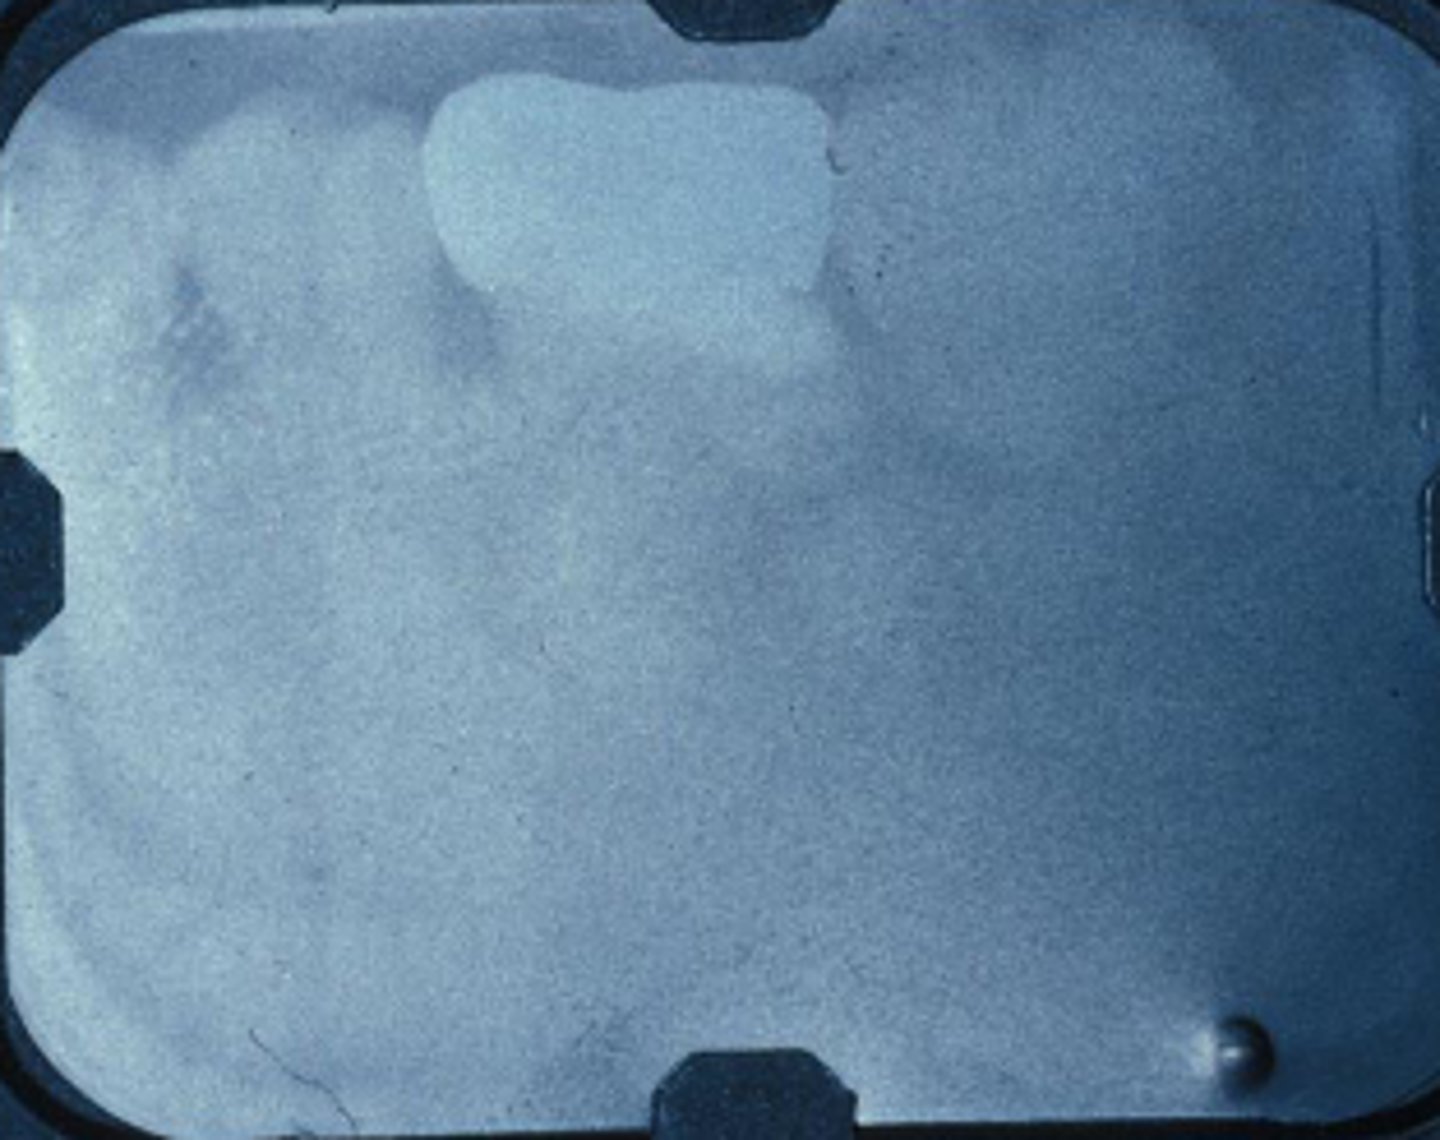

What error occurred here?

Developer time or temperature is too low

What error occurred here?

- Fixer time or temperature too low

- Radiograph opaque

What error occurred here?

- Fixer time or temperature too high

- Radiograph light